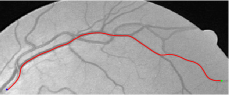

Compare to existing minimal path models. The Riemannian metrics used in [1, 4, 5] are based on the local pointwise information. The curvature-penalized metric [7, 6] and the proposed coherence-penalized metric are able to consider more constraints, i.e., the rigidity for [7, 6] and feature coherence for our metric. These constraints are beneficial to the respective geodesics to reduce the risk of short branches combination problem. Compared to the curvature-penalized metric, our method can be more flexible since the feature map can be produced dependently on the task. In retinal imaging, veins and arteries are distinguishable in terms of gray levels or vesselness values, satisfying the formulation of the proposed model. Especially for vessels with strong tortuosity, the curvature-penalized metric, which favours a smooth curve, fails to catch the expected vessels as shown in the left column of Fig. 2. From the right column of Fig. 2, one can see that our model can obtain a good result.